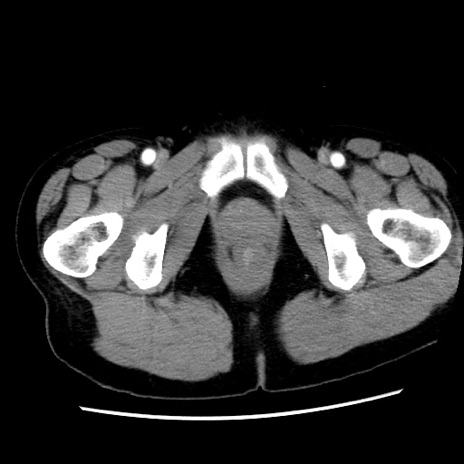

症例10(横断像)

【症例】 50歳代女性

【主訴】 腹痛

【現病歴】前日生レバーを食べた。今朝に排便あり。 昼前に突然発症の腹痛を生じ、当院救急外来を受診した。

【既往歴】 子宮筋腫にてで子宮全摘後

【身体所見】 意識清明、腹部:平坦、軟、下腹部やや左を中心に圧痛・反跳痛あり、筋性防御あり

【データ】WBC 7800、CRP 0.07